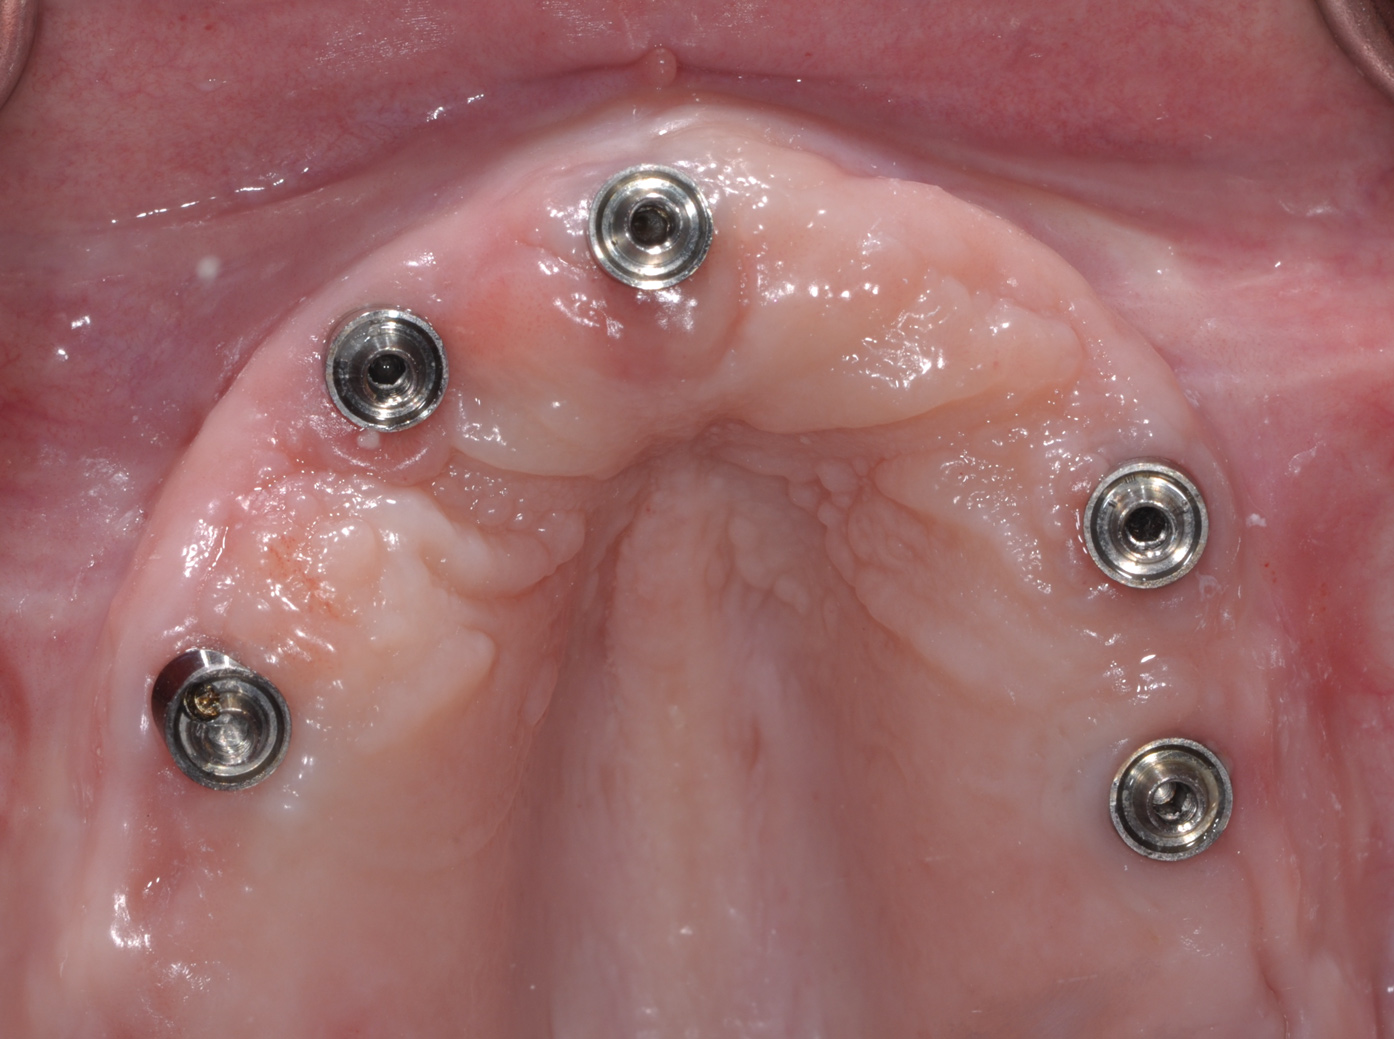

Following the diagnosis of peri-implantitis (Figure 5 and Figure 6), an initial evaluation of the affected implant fixture should be made to establish the rationale for treatment and whether removal of the implant is indicated. Although nonsurgical treatment of peri-implantitis may not always be successful, it should always precede surgical therapy, as this will provide the clinician time to assess the patient's oral hygiene status and response to therapy.22 The primary goal of surgical treatment of peri-implantitis is the decontamination of the denuded implant surface. Multiple surface decontamination protocols have been described in the literature; however, to date, none have shown superiority.23

Fig 5. In this patient, deep probing depths, suppuration, and bleeding on probing were identified.

Figure 5

Fig 6. Radiographic bone loss confirmed the diagnosis of peri-implantitis.

Figure 6